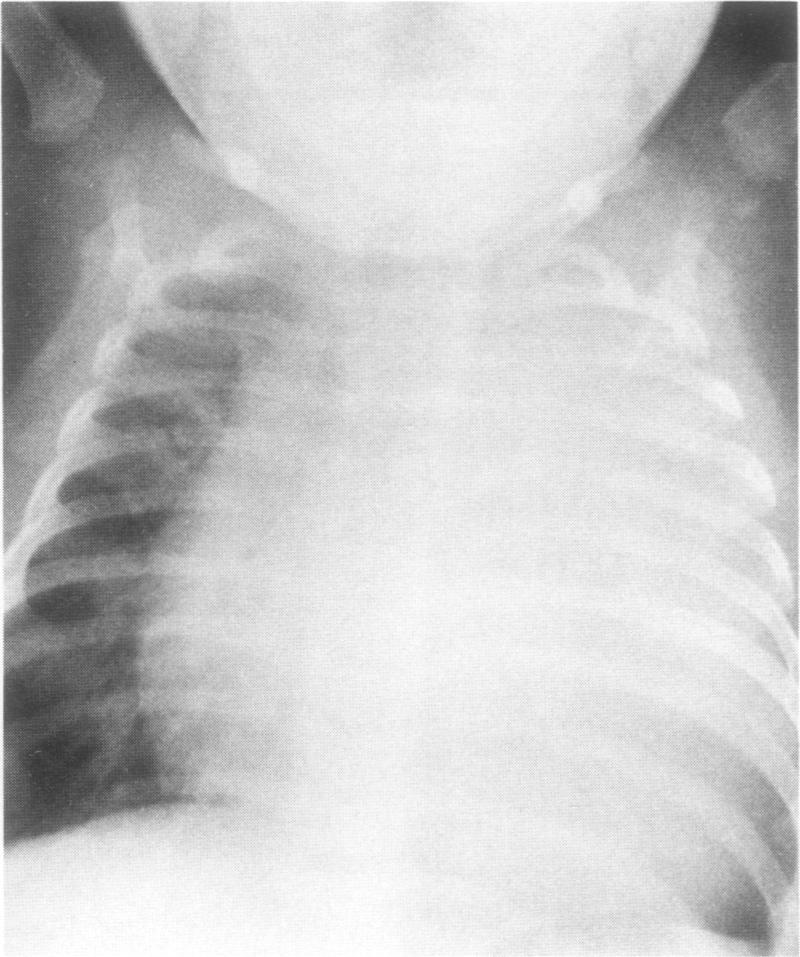

In the case presented here of a 2-month-old boy with symptoms of upper respiratory infection, the physical examination, chest X-ray film and electrocardiogram led us to suspect congestive heart failure caused by either a primary or infectious cardiomyopathy or by a structural left ventricular outflow tract obstruction. The echocardiographic findings were the first evidence to suggest the presence of an intracardiac tumor. A cardiac computerized axial tomography scan supported the findings. Operation was performed, but the tumor was unresectable. Biopsies of the mass revealed fibromatosis. The infant was discharged on diuretics, procainamide and propranolol. Approximately 3 weeks following discharge, while at rest, the child suddenly became unresponsive and could not be resuscitated. Postmortem examination verified the degree of precision that can be achieved by noninvasive techniques.